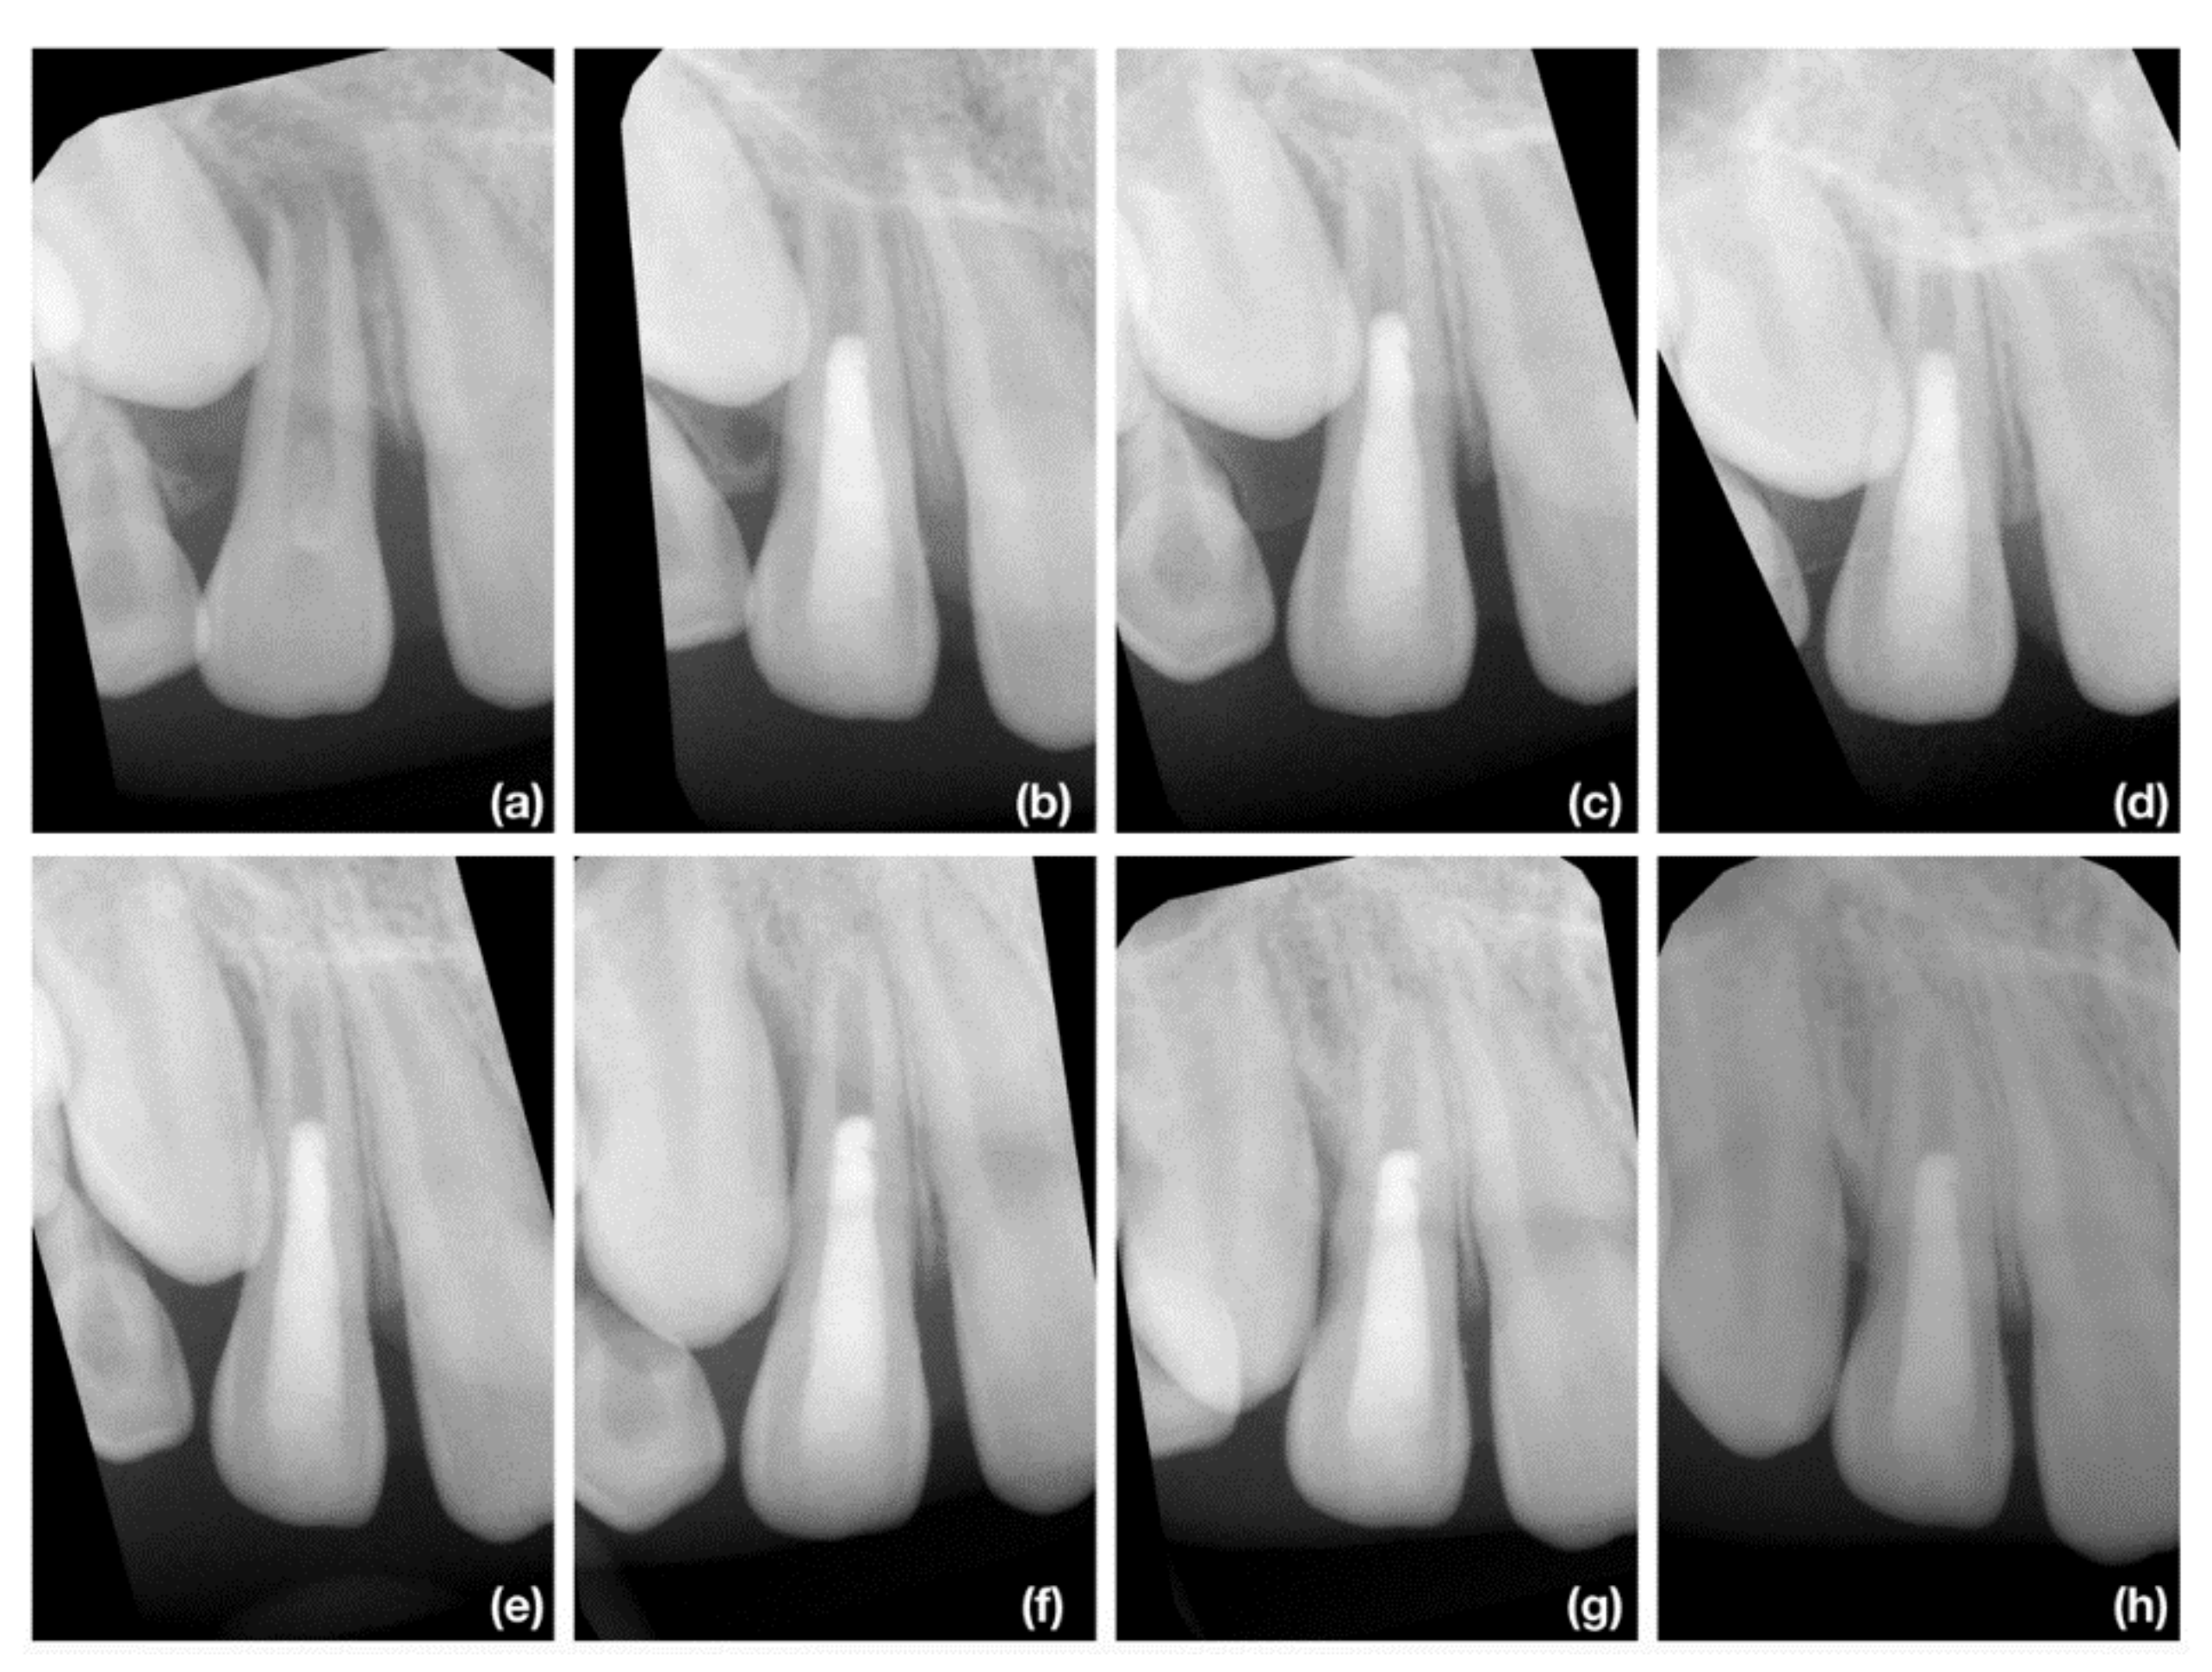

2.4. Radiographic Assesment

2.4.2. Radiographic Root Length Measurement

2.4.3. Radiographic Root Width Measurement

2.4.4. Radiographic Root Area Measurement

3.2. Radiographic Root Length Change

3.3. Radiographic Root Width Change

3.4. Radiographic Root Area Change

3.6. Periapical Index Change